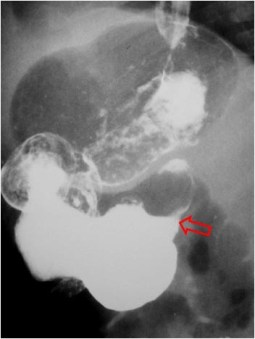

SIGNO DEL PSEUDOTUMOR DUODENAL

Es un signo de significado similar al Signo del pseudotumor fúndico (Ver Otros signos de estómago en https://album-de-signos-radiologicos.com/category/estomago/otros-signos-de-estomago/).

En la radiografía simple de abdomen, el bulbo duodenal lleno de líquido produce una imagen nodular o pseudotumoral, tal como vemos en la imagen (flecha). No debe confundirse con una litiasis biliar, que ocupa una posición similar pero que, cuando es visible, es porque tiene una densidad cálcica.

Este signo también se ha llamado Signo del pseudotumor del hipocondrio derecho.